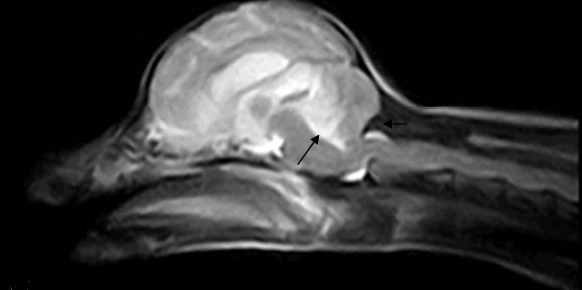

| T2 |

|---|

![]() |

| (MRI์์๋ ๊ฒ์ ๊ฒ ๋ผ.) ์์์ ํ๋๋ถ์ ๋ผ๊ฐ ์๋๋ฅผ ๋๋ฅด๊ณ ์์ (COMS) + ์๋์ชฝ์์ C1์ด ์ฒ์๋ฅผ ์ฐ๋ฅด๊ณ ์์ (kinking) |

์์๋์์ ๋๋ ค์ CSF์ blood flow๊ฐ ๋ฐฉํด๋ฐ์. โ Cerebellar infarction.

โ Caudal occipital Malformation Syndrome(COMS). = Chiari-like syndrome.

- Hyper-intense on the right and rostral cerebellum, and has a wedge-shaped appearance. hypo-intense(T1).

- Rostral displacement of the caudal cerebellum by the occipital bone.

- This feature appers COMS.